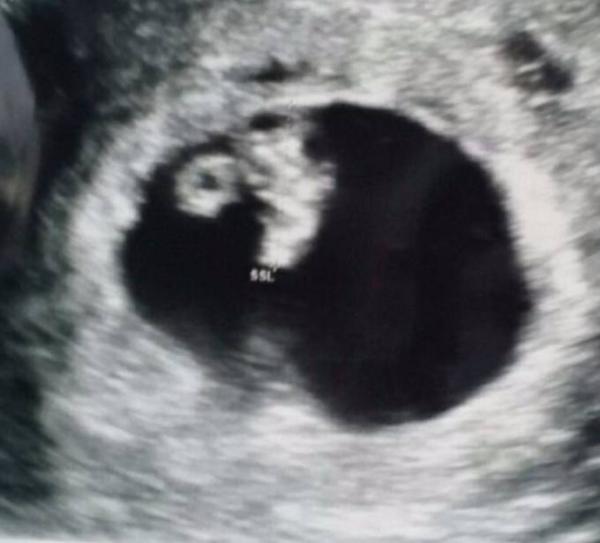

Klar lässt es sich jetzt alles nur spekulieren bis zum nächsten FA Termin, aber eine Bekannte (Hebamme) meint, dass mein Bildchen nach Zwillingen aussieht, das eine eben etwas versteckter ist. (7+1ssw)

Meinst du oben rechts im Bild was aussieht als wären da noch kleine Fruchthöhlen zu der Großen dazu?

Ja genau. Wobei es mich wundert, weil sie eben viel kleiner ist.

Also bei mir hat man eine Fruchthöhle auch nur kleiner gesehen, weil sie hinter der anderen lag. Meine Ärztin meinte, dass beide aber gleich seien, man es derzeit auf dem US aber nicht besser sehen kann. Sonst müsste sie zu sehr rumdrücken. Hättest du gerne Zwillinge?

Hmmm ich weiss nicht, ich kenne mich da nicht aus. Ich hatte bei der letzten Untersuchung auch so eine kleine Höhle neben der großen Fruchthülle. Die Ärztin meinte das wäre ein kleines Blutkoagel. Nichts schlimmes, ganz harmlos. Also schadet der Schwangerschaft nicht.